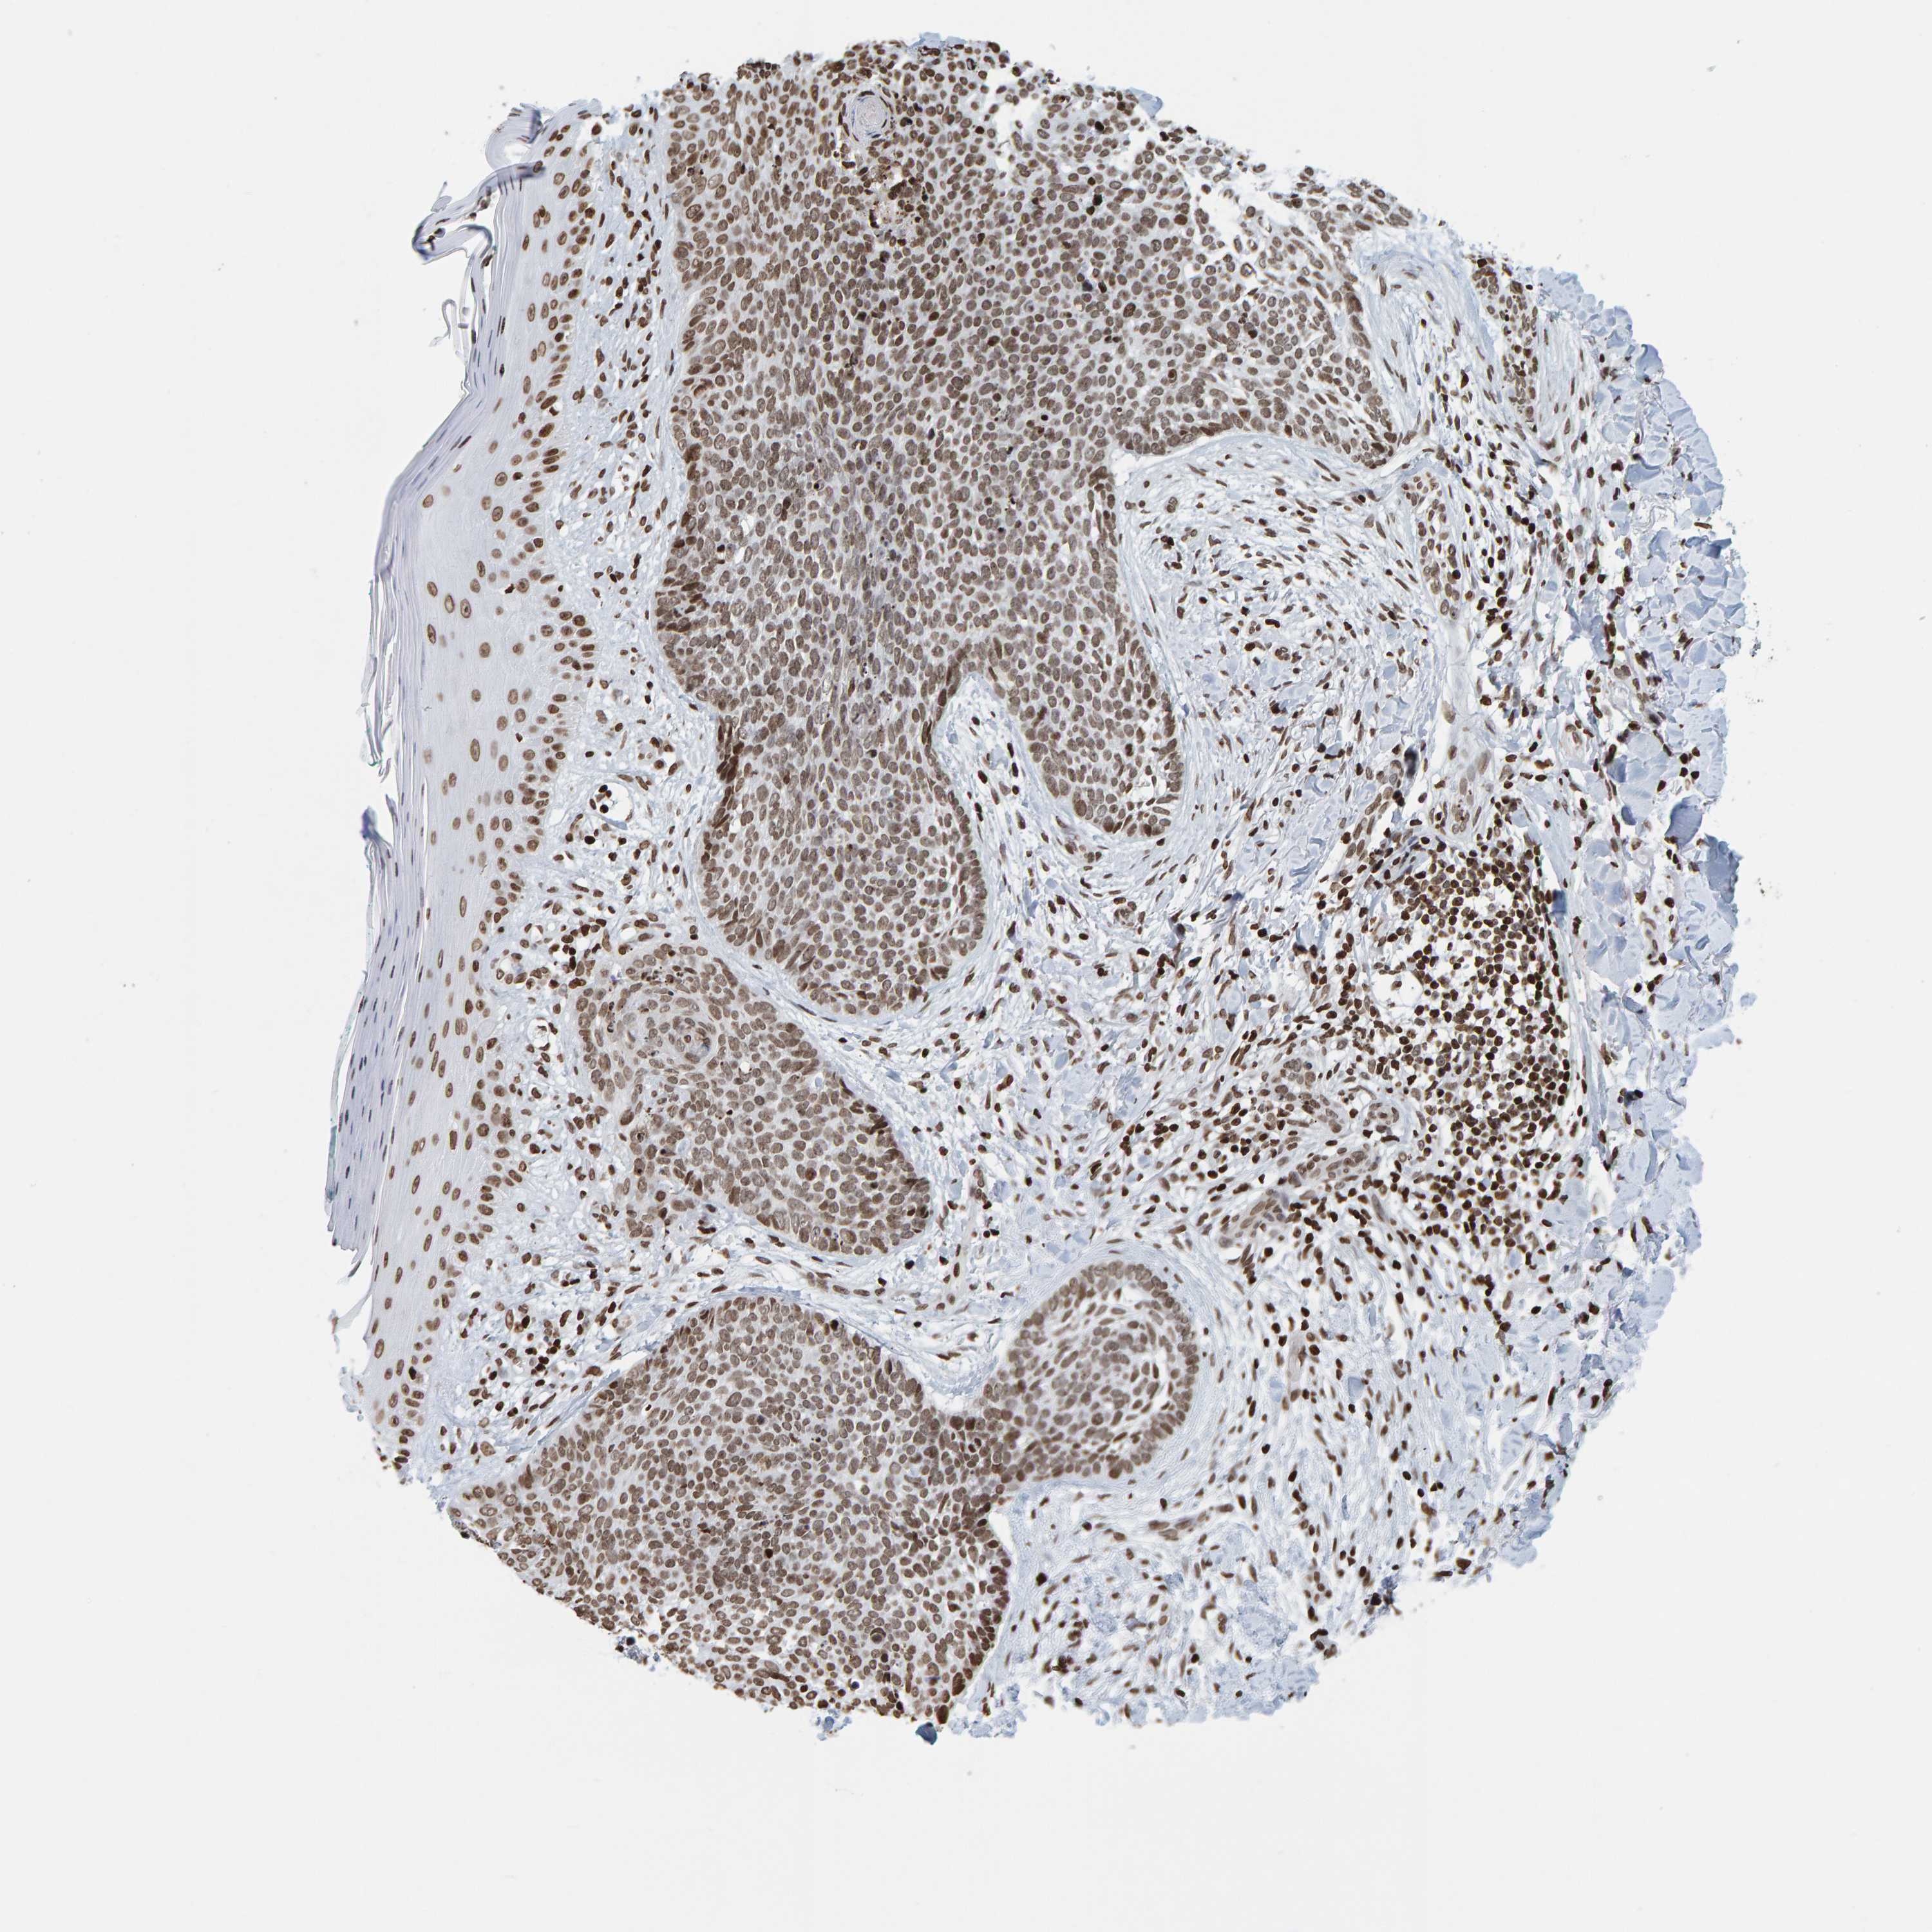

SKIN CANCER - Protein expressioni

A mouse-over function shows sample information and annotation data. Click on an image to view it in a full screen mode. Samples can be filtered based on level of antibody staining by selecting one or several of the following categories: high, medium, low and not detected. The assay and annotation is described here.

Each image is clickable and will lead to virtual microscopy that enables deeper exploration of all samples and also displays staining intensity scores, fraction scores and subcellular localization as well as patient and tissue information for each sample.

Antibody HPA023378

Basal cell carcinoma